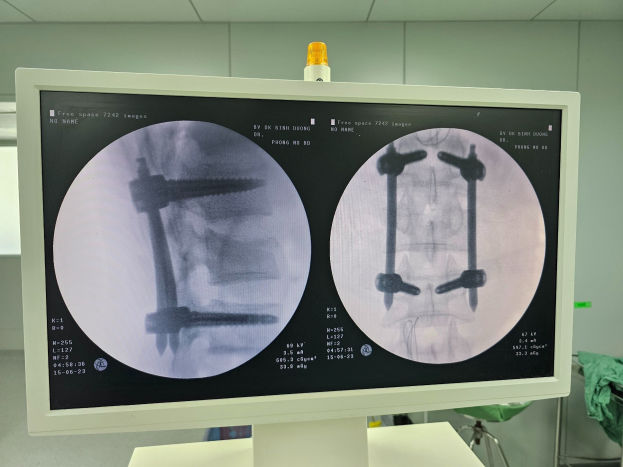

| Hình ảnh C-Arm sau mổ gãy cột sống thắt lưng bằng phương pháp bắt vít qua da. |

Vừa qua, ngày 15/06/2023 Bệnh viện đã tiếp nhận và phẫu thuật thành công cho bệnh nhân ( nam, 23 tuổi) bị tai nạn giao thông. Kết quả chụp phim chẩn đoán trước mổ: Gãy cột sống L2 nhiều mảnh và được chỉ định phẫu thuật bắt vít cố định cột sống qua da. Sau phẫu thuật sức khỏe bệnh nhân phục hồi tốt, đã có thể đứng dậy đi lại bình thường, không đau vết mổ.